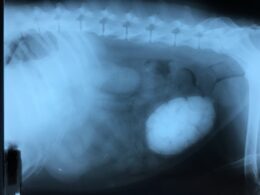

Small Animal Imaging

Sometimes, it requires a look inside to find what is troubling your pet. We have high-quality digital radiography (x-ray) capability, so we can see a tooth abscess that is under the gums, or a broken bone in the foot, or the engagement ring your dog swallowed.